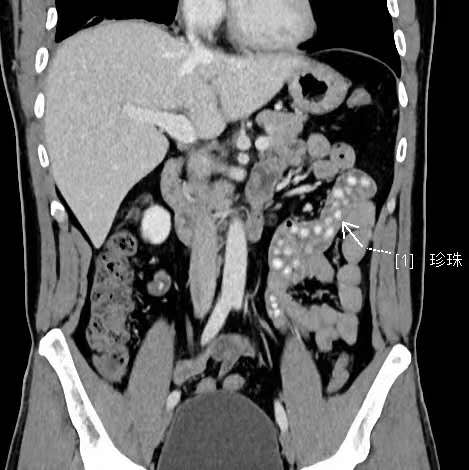

拍出來的片子讓醫(yī)生大吃一驚,小林的胃腸道里布滿了高密度陰影。仔細一看,醫(yī)生發(fā)現(xiàn)是一顆顆沒有消化的東西,像珍珠奶茶里面的“珍珠”。

“密密麻麻,粗略估計有幾十顆。”影像科副主任醫(yī)師薛貞龍告訴現(xiàn)代快報記者,奶茶里的珍珠很難消化,CT顯示腸腔內(nèi)圓形結(jié)節(jié)狀高度密影。他提醒,對于炎性腸病患者,尤其是伴有輕中度腸道狹窄的患者,最好別喝奶茶,很容易誘發(fā)腸梗阻。